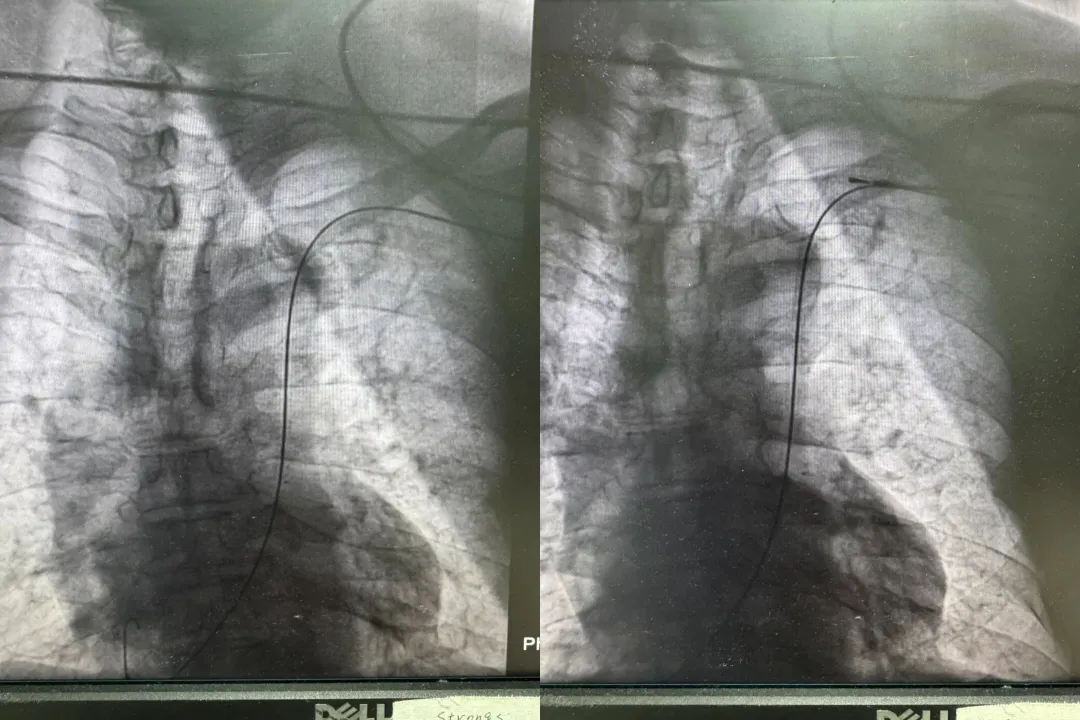

面对这一危急情况,心内一科团队迅速制定治疗方案,并依托与医生集团的常态化协作机制,特邀北京安贞医院戴文龙主任前来指导并主刀手术。术中,团队发现患者存在“永存左上腔静脉”这一罕见的血管解剖变异,显著增加了手术难度与风险。戴文龙主任凭借丰富的起搏器植入经验,沉着应对,精细操作,仅用一小时就成功将起搏电极放置到位,并顺利植入起搏器。术中测试显示,起搏信号清晰、感知良好、各项参数均达理想标准,为患者建立起一道坚实的“生命防线”。